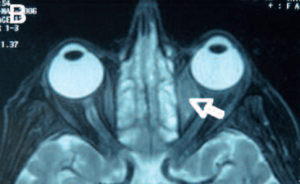

Orbital lymphoma

Orbital lymphoma is a common type of non-Hodgkin lymphoma that occurs near or on the eye. Common symptoms include decreased vision and uveitis. Orbital lymphoma can be diagnosed via a biopsy of the eye and is usually treated with radiotherapy or with combination with chemotherapy.